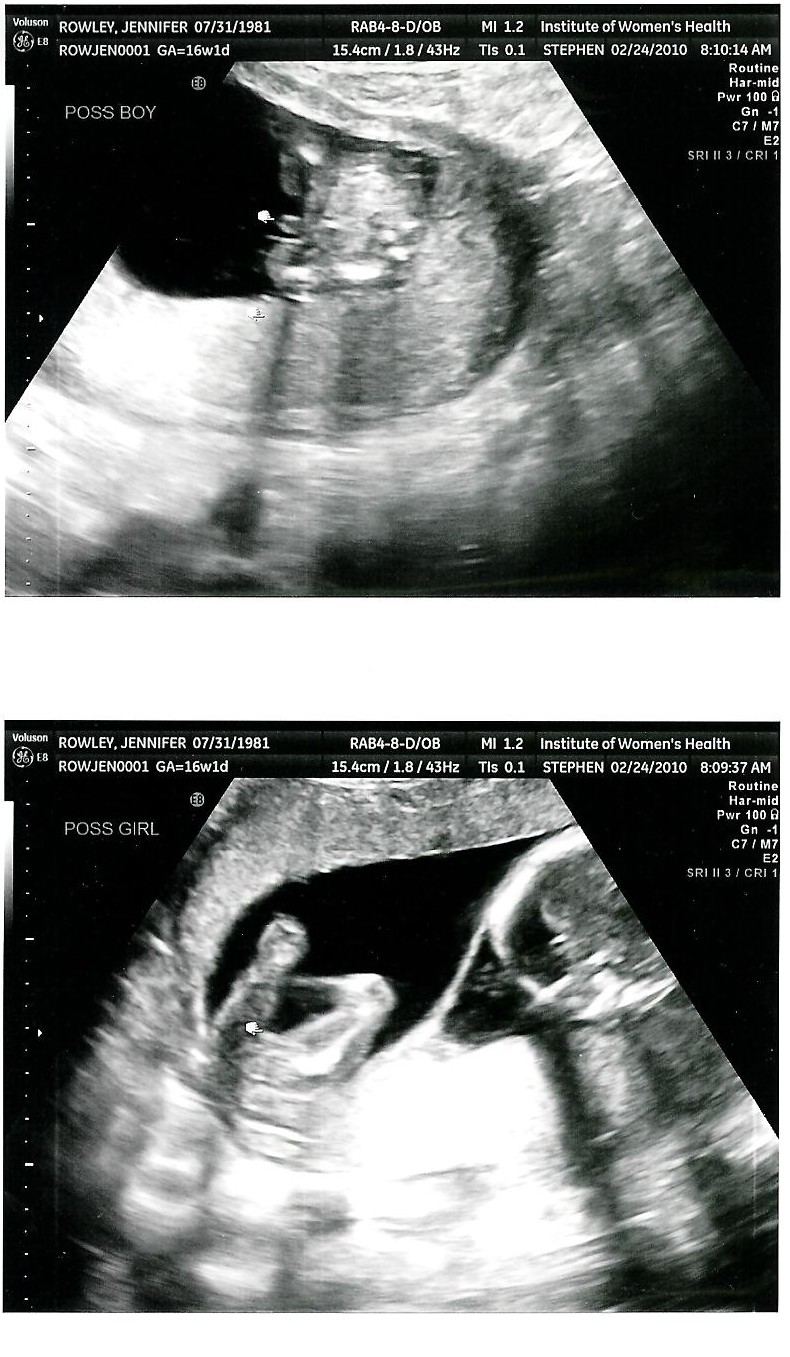

Twin Parenting Twin ultrasound 8 weeks

From twin-mommy-blog.blogspot.hu

Twin Parenting Twin ultrasound 8 weeks Can You Have Twins And Not Show On Ultrasound For example, perhaps a hidden twin was. Let’s talk about several factors that. Twins can typically be detected on ultrasound during the first trimester, usually around 6 to 8 weeks of gestation. hidden twins can be detected through regular ultrasound examinations during pregnancy. Here are some commonly asked questions about when your twins may be seen on. When do. Can You Have Twins And Not Show On Ultrasound.